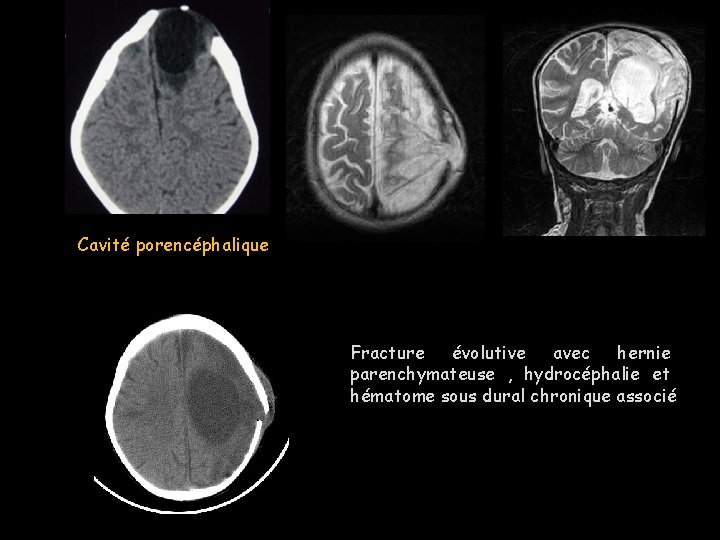

Fracture évolutive • Enfant < 3 ans , • Traumatisme sévère, ou obstétrical (forceps) ou chirurgie craniofaciale. • Délais variable Radiographie conventionnelle -Trait de fracture souvent linéaire, -large > 3 mm. TDM - Contusion corticale. -Etendue en profondeur, avec hématome péricérébral.

- - L’IRM Seule imagerie affirmant le diagnostic dès la période initiale: Brèche méningée , hernie parenchymateuse à travers la fracture. En T 2 : une zone linéaire en iso signal au LCS interrompant les tables osseuses; Plans perpendiculaires au trait de fracture +++ - À un stade plus tardif: - Gliose parenchymateuse, kyste porencéphalique - Dilatation ventriculaire homolatérale

bébé après accouchement par forceps: fracture évolutive de l'os pariétal droit avec hernie d'une partie du lobe pariétal.

Cavité porencéphalique Fracture évolutive avec hernie parenchymateuse , hydrocéphalie et hématome sous dural chronique associé

Important+++ • Tout enfant surtout âgé de moins de 3 ans, avec un trait de fracture du crâne large, doit être surveillé cliniquement dans les mois suivant un traumatisme crânien pour ne pas méconnaître une fracture évolutive